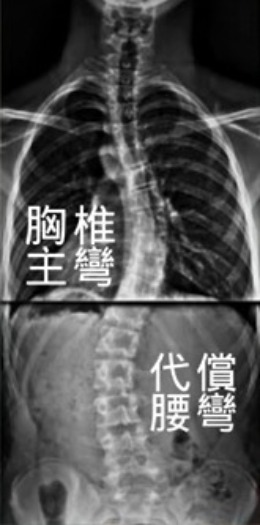

2. 評估是否有「代償彎」產生

臨床常見 S 型側彎,即同時存在主彎與代償彎。

綜合考量: 臨床上我們常常可以看到S型的側彎,即出現了2個彎弧。此時,就需要判斷哪個是主彎,哪個是代償彎。例如,同樣是胸彎類型(胸彎為主彎),若腰椎有明顯的代償彎,運動的方式就要做改變。若只針對胸部主彎訓練而忽略腰部代償,沒有相應的預防措施,可能會發生「胸彎改善了、腰彎卻惡化」的遺憾。